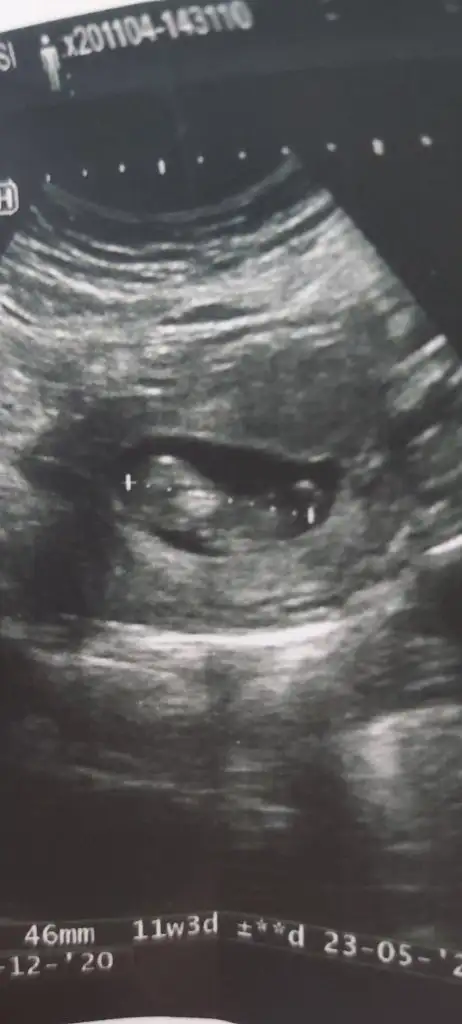

Merhaba hanımlar bende tahmin alabilir iyim 11+3 hamileyim.

Eklentiler

• IMG_20201104_180315.webp

17,4 KB · Görüntüleme: 67